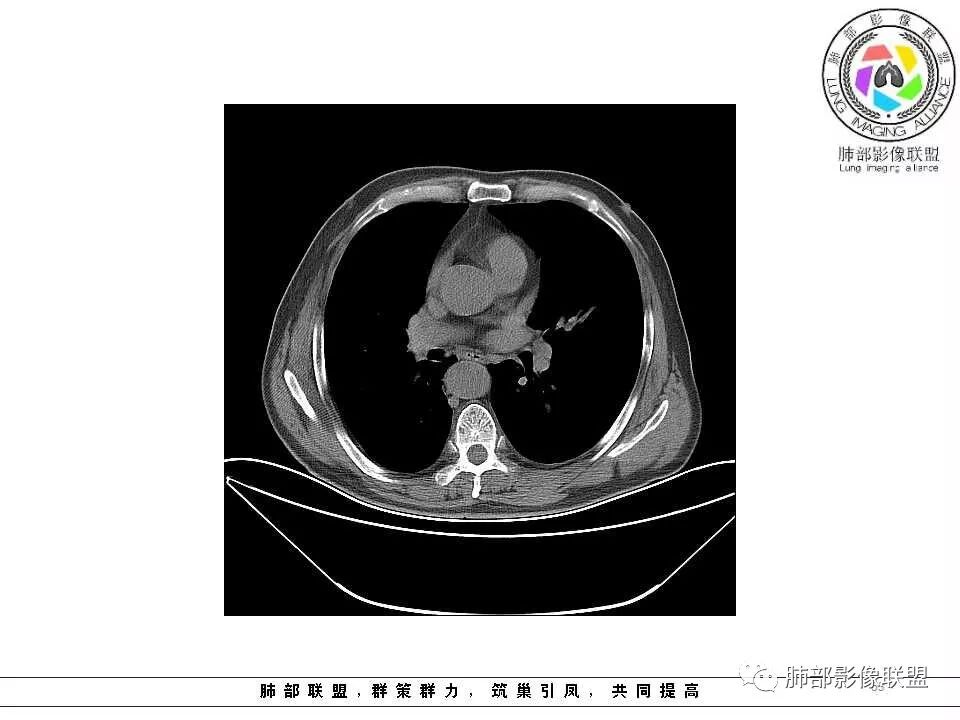

老年男性,两肺可见小叶中央型肺气肿,提示应该有抽烟史。2016年片,右肺门支气管稍模糊,考虑慢性感染,纵膈淋巴结稍大。但2017年左肺上叶新发占位,堵塞支气管,引起局部肺不张伴感染,且纵膈淋巴结较2016年变大,患者同时伴有咯血,考虑恶性。鳞癌?类癌?小细胞?

肺气肿背景,2016年左肺上叶上舌段见微结节,2017年5月左肺结节增大,密度均匀,边缘光滑锐利,与邻近血管关系密切,血管贴壁走行,外侧见尖状突起,下舌段片状影,沿着支气管走行,内有粘液栓,考虑鳞癌,鉴别小细胞肺癌。

肺气肿背景,2016年左肺上叶上舌段见微结节,一年后左肺结节增大,密度均匀,边缘光滑、膨隆,似见小分叶,下舌段片状影,沿着支气管走行,内,老年患者,咯血1月。考虑恶性病变并阻塞性肺炎,鳞癌?注意鉴别结核。